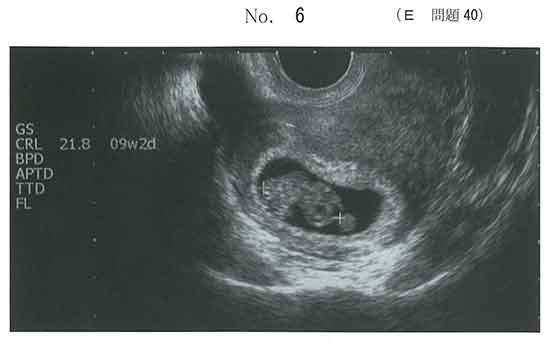

頭殿長ではかったら最終月経と比べて3週遅いから。

画像に9w2dと書いてあるのを信じてd

CRLで補正するので3週遅らせてdにしました

Dです